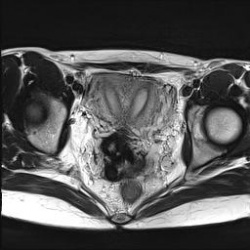

Полное удвоение матки. Случайная находка. Женщина рожавшая, была весьма удивлена.

24.06.2010 - 18:08

Достаточно редкое наблюдение - интрамуральная липома матки. T2 T1 Fat Sat

24.06.2010 - 17:51

Женщина, 40 лет. Жалобы на острые боли в малом тазу.Ваше мнение? Постконтрастный: